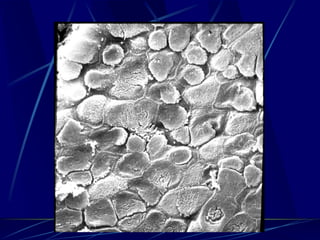

Lung Skeleton

 Force-bearing structure

 Elastin and collagen that are embedded in

a the extracellular matrix

 Two fiber systems connected at alveolar

levels one originating from the hilum and

the other from the visceral pleura in the

periphery

Papadakos, Karcz and Lachman Mechanical Ventilation in Trauma, Curr Opin in

Anesthesiol 23 2010

Microstructure